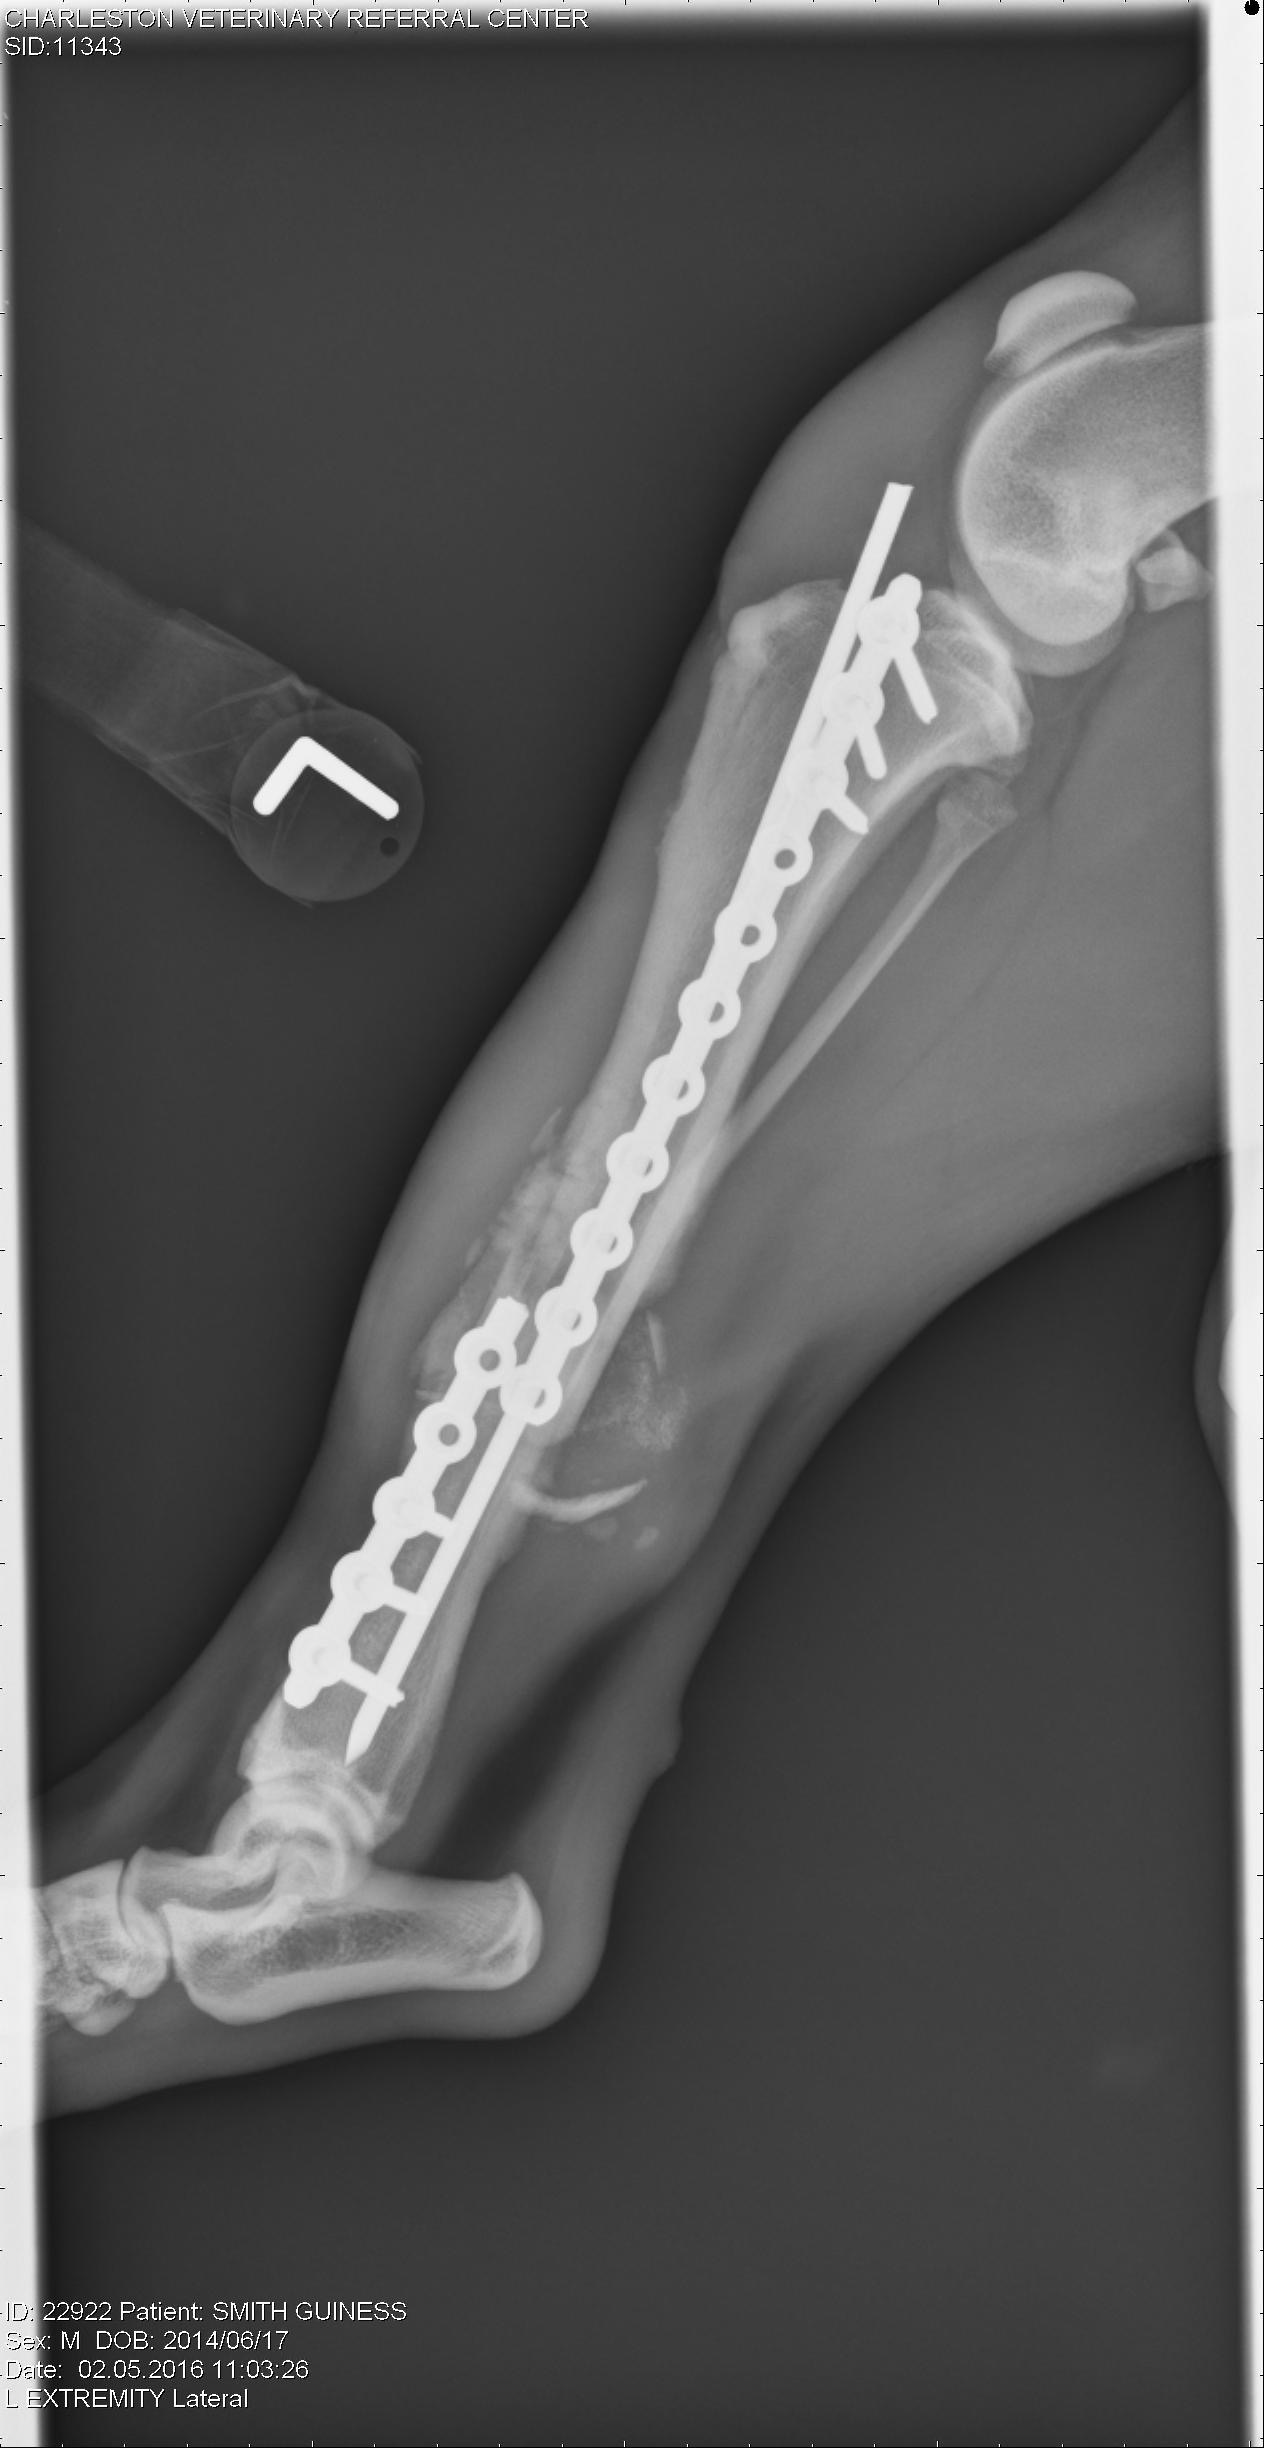

Our boy Guinness has had a heck of a time. BUT, we are EXCITED to report his fracture has healed beautifully and his Orthopedic Surgeon has given him a clean bill of health without any restrictions! Thus helping him find his perfect Forever Home.